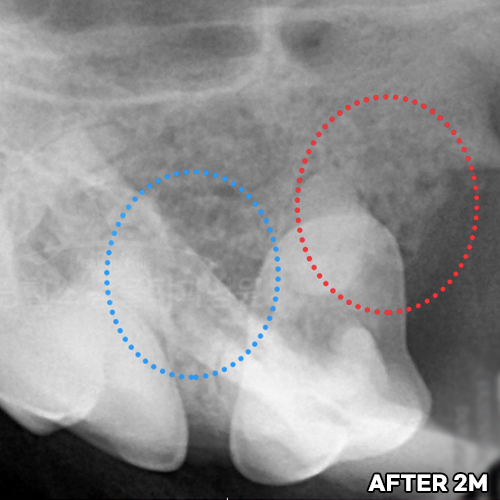

[강아지잇몸뼈 치료 후 2달 경과]

[강아지잇몸뼈 재생치료 하고 재생된 자기 잇몸뼈]